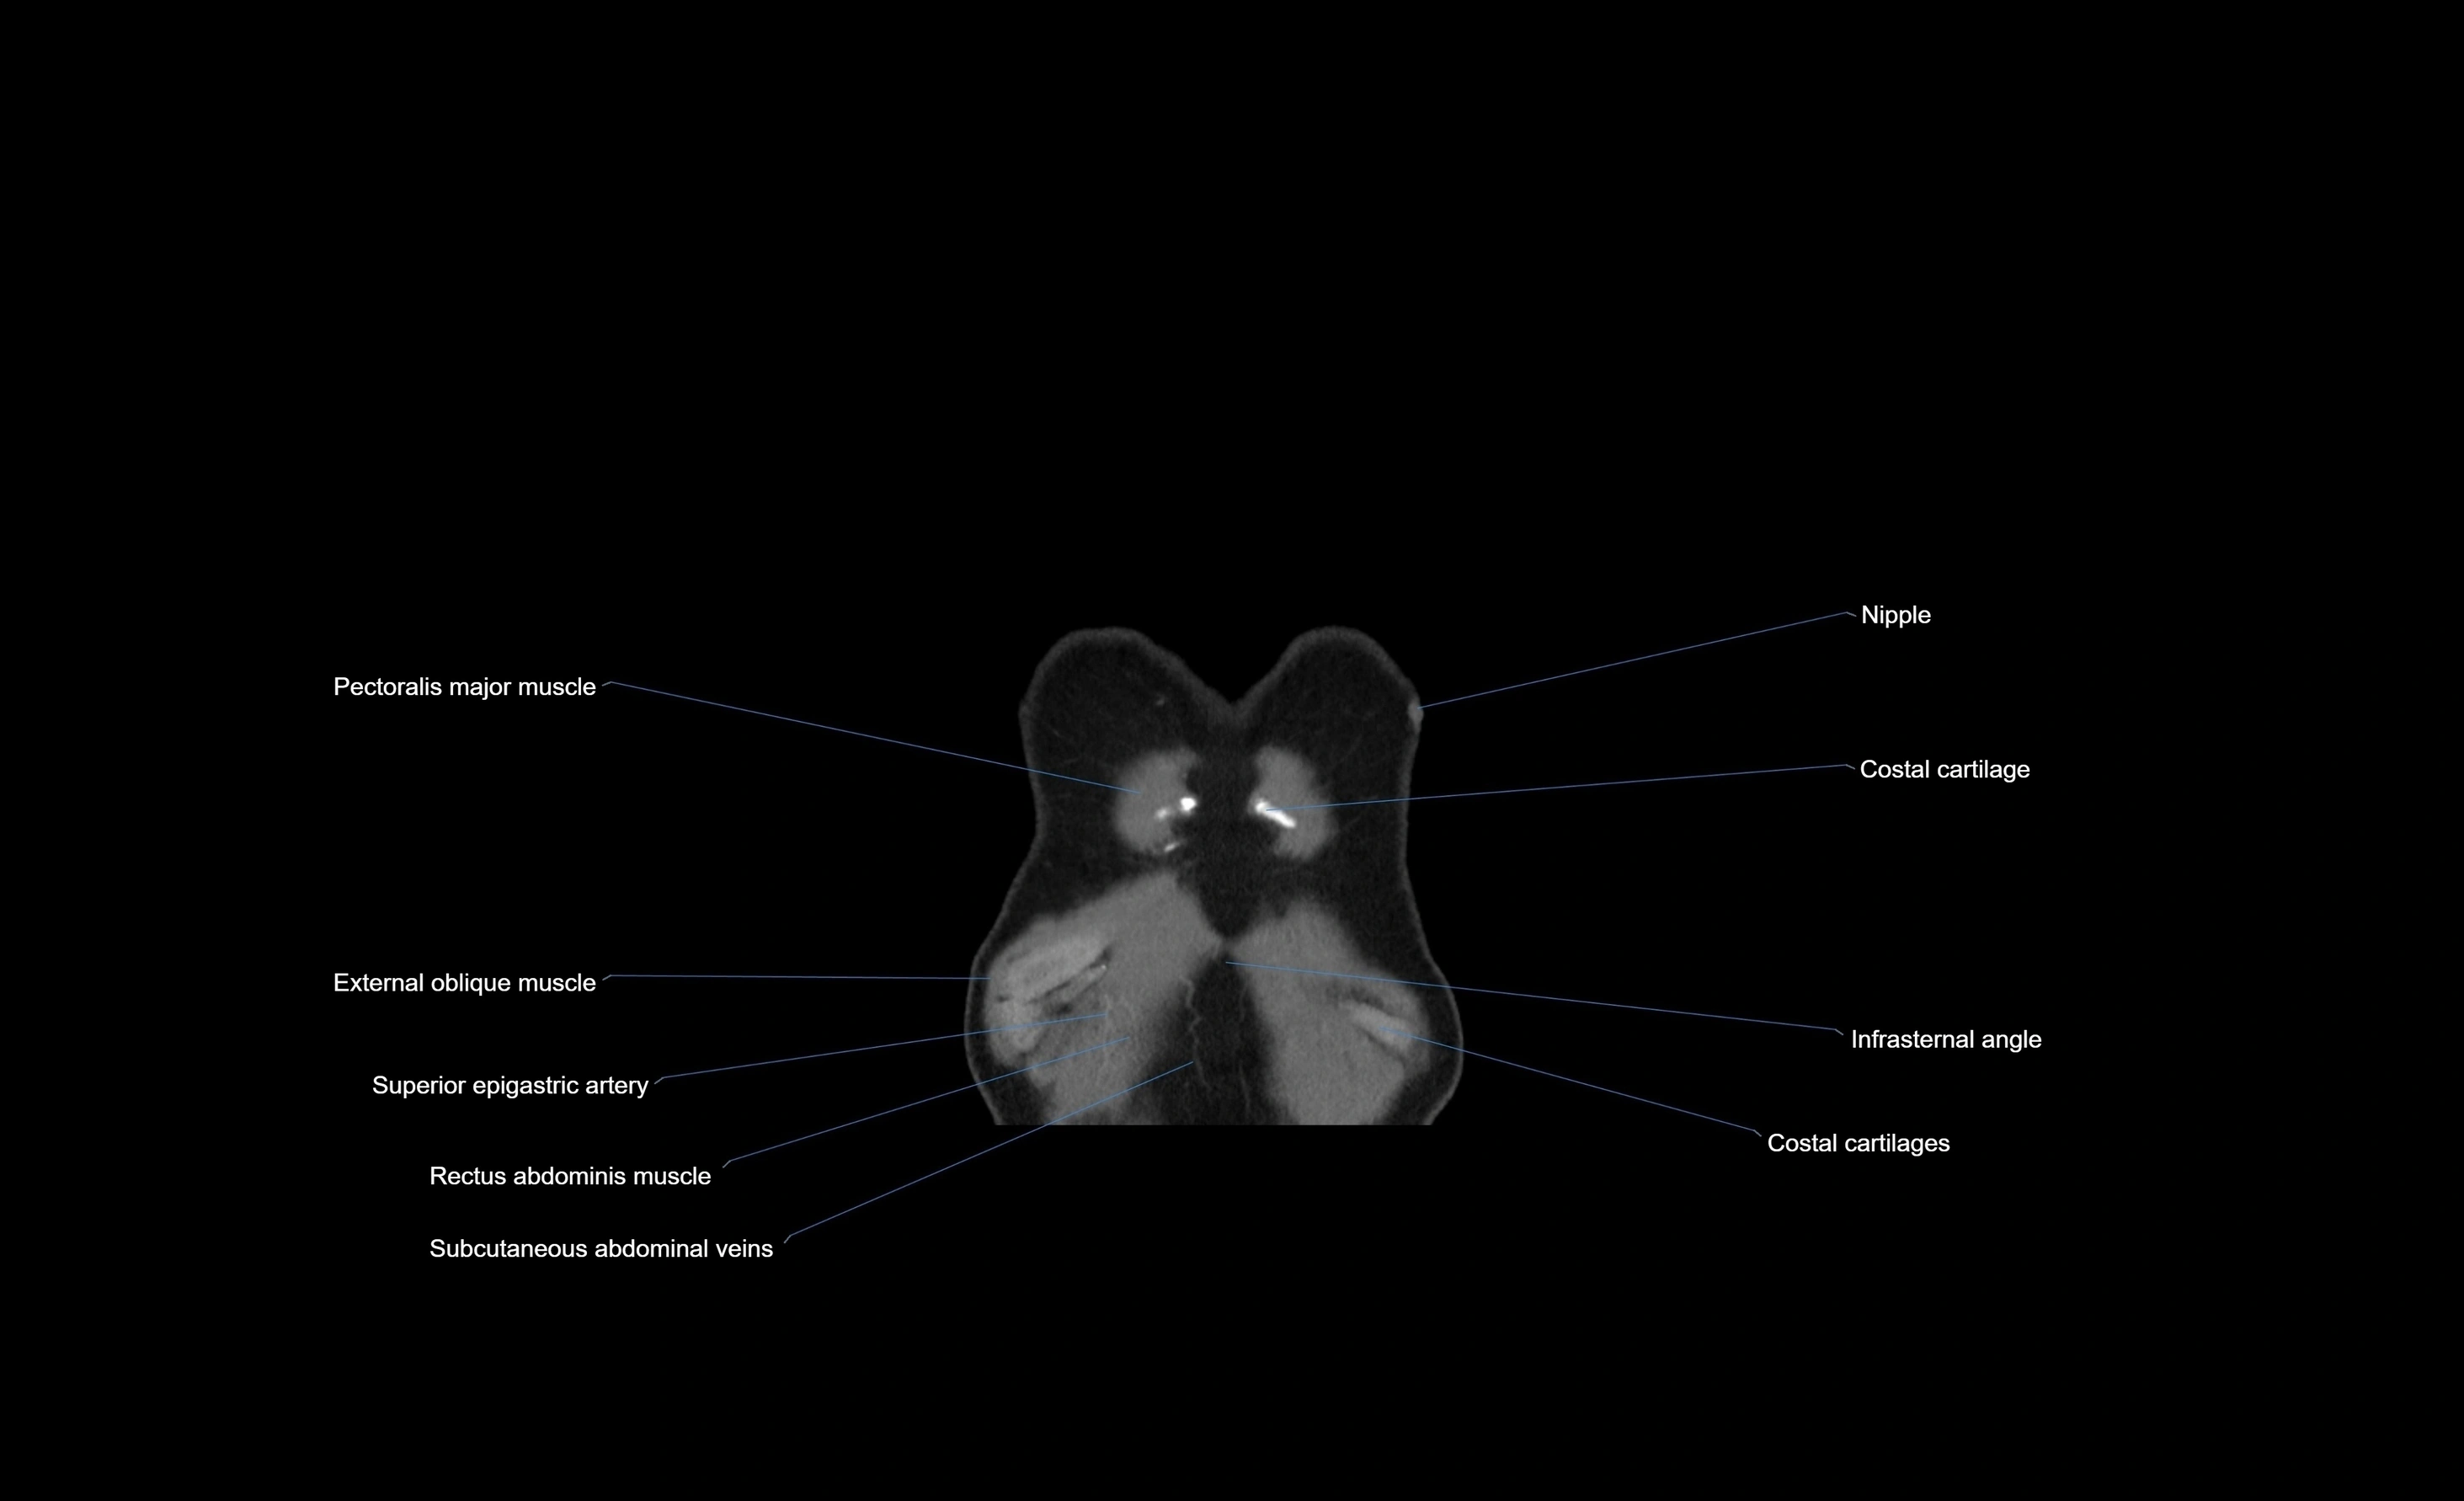

- Costal cartilages

- External oblique muscle

- Rectus abdominis muscle

- Superior epigastric artery